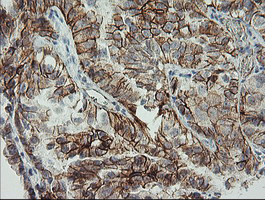

Immunohistochemical staining of paraffin-embedded Adenocarcinoma of Human ovary tissue using anti-CDH2 mouse monoclonal antibody. (Heat-induced epitope retrieval by 10mM citric buffer, pH6.0, 100°C for 10min, M01577-5)